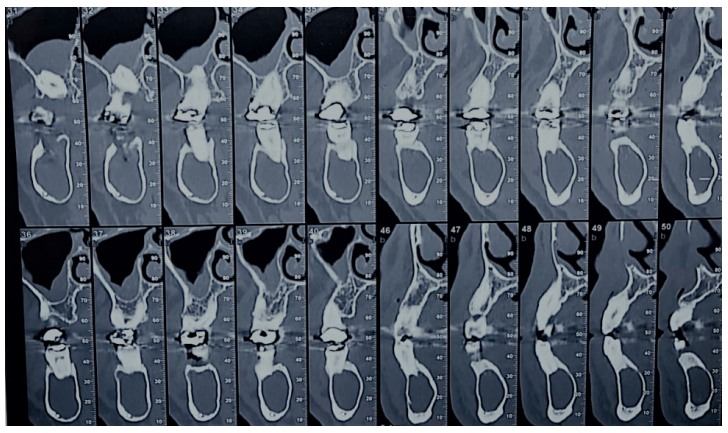

Acudió a servicio de cirugía oral, derivado por su odontólogo, un paciente varón de 65 años sin antecedentes médicos de interés, tras comprobar un importante crecimiento de una imagen radiotransparente respecto a última radiografía de hacía 5 años. El paciente no refirió sintomatología asociada. A la exploración extraoral no se apreció ningún tipo de deformidad ni afectación ganglionar. A la exploración intraoral pese a que se constató la integridad de las corticales, las cuales no estaban abombadas, sí que se pudo apreciar a la palpación un signo positivo de Dupuytren o de “Ping-Pong”. Además se constató una falta de afectación de los dientes del cuarto cuadrante que no presentaban movilidad y tenían una vitalidad positiva (Figura 1). Como complemento a la exploración clínica se solicitó un estudio mediante TAC, donde se apreció la extensión de una lesión radiotransparente que afectaba a rama y cuerpo mandibular derecho. (Figuras 2 y 3).

La cirugía se planteó bajo sedación y con el doble objetivo de la eliminación completa de la lesión con el cordal asociado y evitar un debilitamiento excesivo de la mandíbula. Para ello, se realizó un triple acceso a la lesión que nos permitiese por un lado despegar el quiste en toda su extensión mediante el uso de periostotomos y cucharillas de legrado, y por otro lado preservase una serie de “arbotantes” óseos que a su vez permitieran la posterior colocación de una mini placa desde la rama mandibular hasta el cuerpo, que actuase como refuerzo estructural (Figura 4).